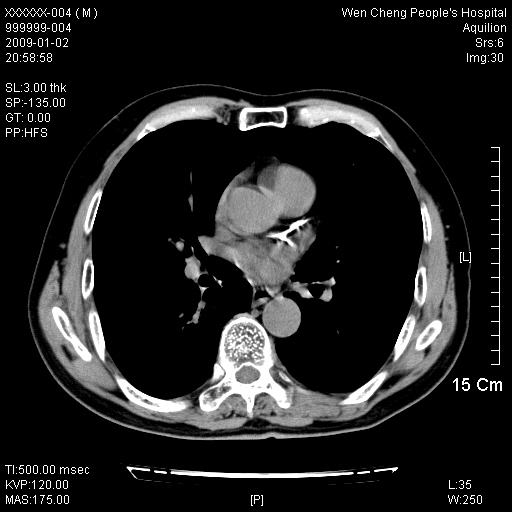

男性,73岁,有慢支病史,肿瘤系列标志物检验正常,血沉及血常规正常

支气管炎,小叶气肿,右下肺局限性炎症并轻度支气管扩张冠脉钙化。

1、慢性支气管炎。

2、右肺下叶片团状影内见扩张的含气支气管和支气管管壁增厚,其周有磨玻璃样模糊影和长毛刺。考虑周围型肺ca可能,结核不排。

3、左右冠状动脉钙化。

机化性肺炎 , 左右冠状动脉钙化。

支气管炎,小叶气肿,右下肺局限性炎症并轻度支气管扩张冠脉钙化